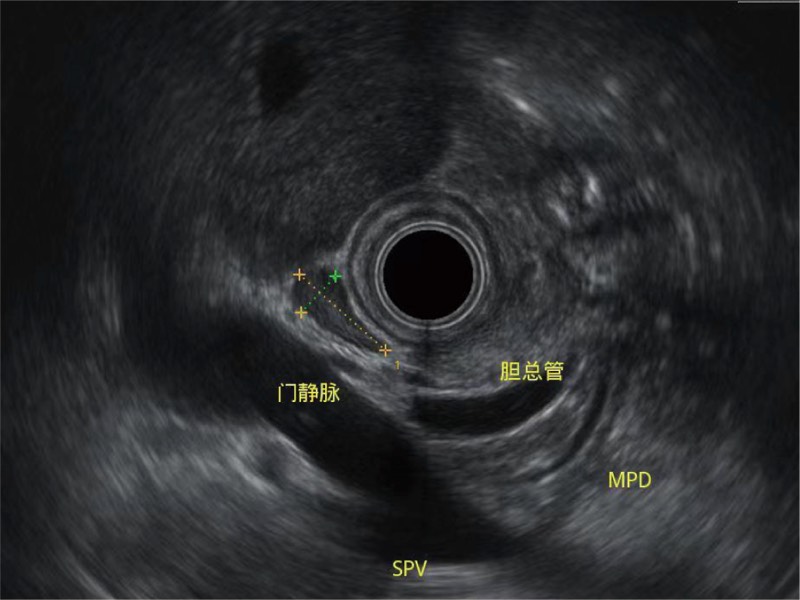

清晰显示胆总管及周围血管分布